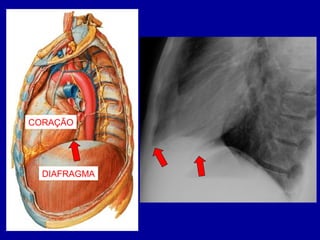

DIAFRAGMA

• SEPARAÇÃO ENTRE

TÓRAX E ABDÔMEN

• DUAS HEMI-CÚPULAS

• DIAFRAGMA DIREITO

MAIS ALTO

CORAÇÃO